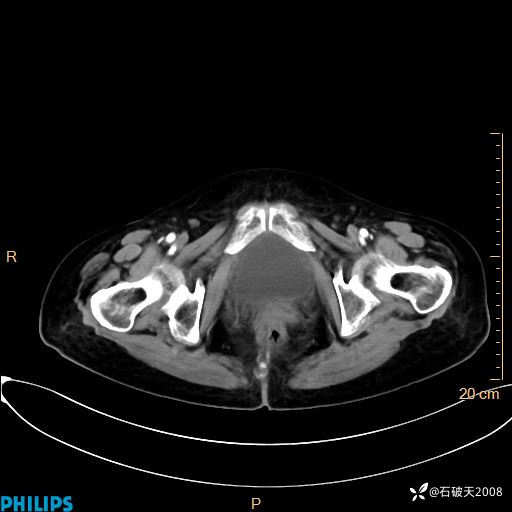

静脉期